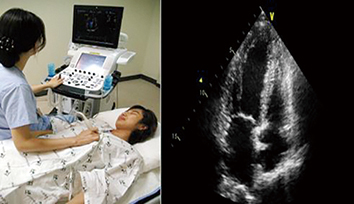

올바른 진단·치료 위한 美 ‘심초음파학회’의 지침

무증상 환자·수술 중 환자 등에 초음파 검사 남용 금지

미국 심초음파학회 American Society of Echocardiography